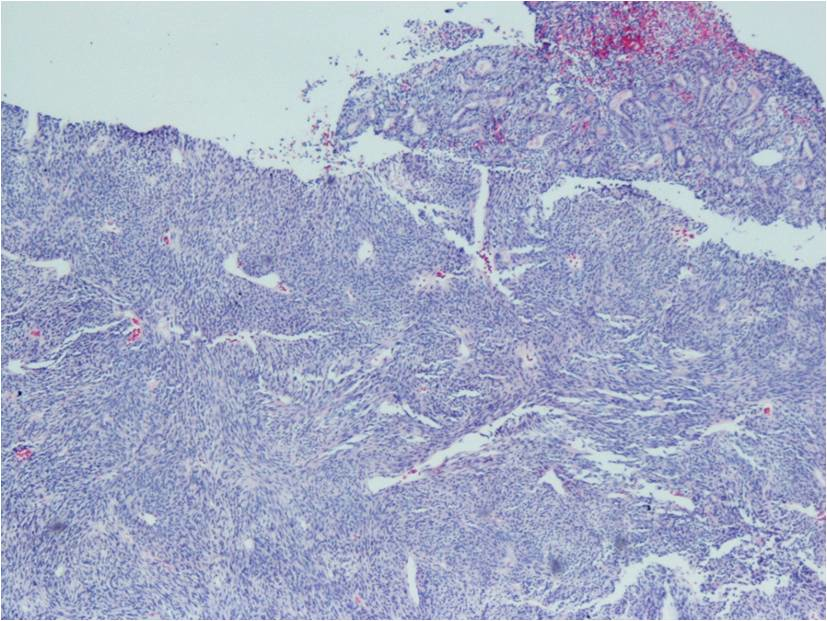

Microscopic Pathology

Synovial Sarcoma is composed of two different cell types

Spindle cell (small, uniform, and ovoid cells with pale nuclei and the cytoplasm is sparse)

Epitheloid cell (ovoid nuclei and abundant cytoplasm)

Biphasic form is composed of both epithelial-cell and spindle-cell components in equal proportions (Fig. 6-8)

Monophasic Fibrous type predominantly spindle cell.

Monophasic Epithelial type is difficult to differentiate from adenocarcinoma without cytogenetics and immunohistochemistry.

Poorly differentiated type demonstrates features of high grade small round cell tumor with dense cellularity, numerous mitotic figures, and areas of necrosis.

Inmunohistochemical profile: Vimentin (+), Cytokeratin (+), Epithelial Membrane Antigen EMA (+)